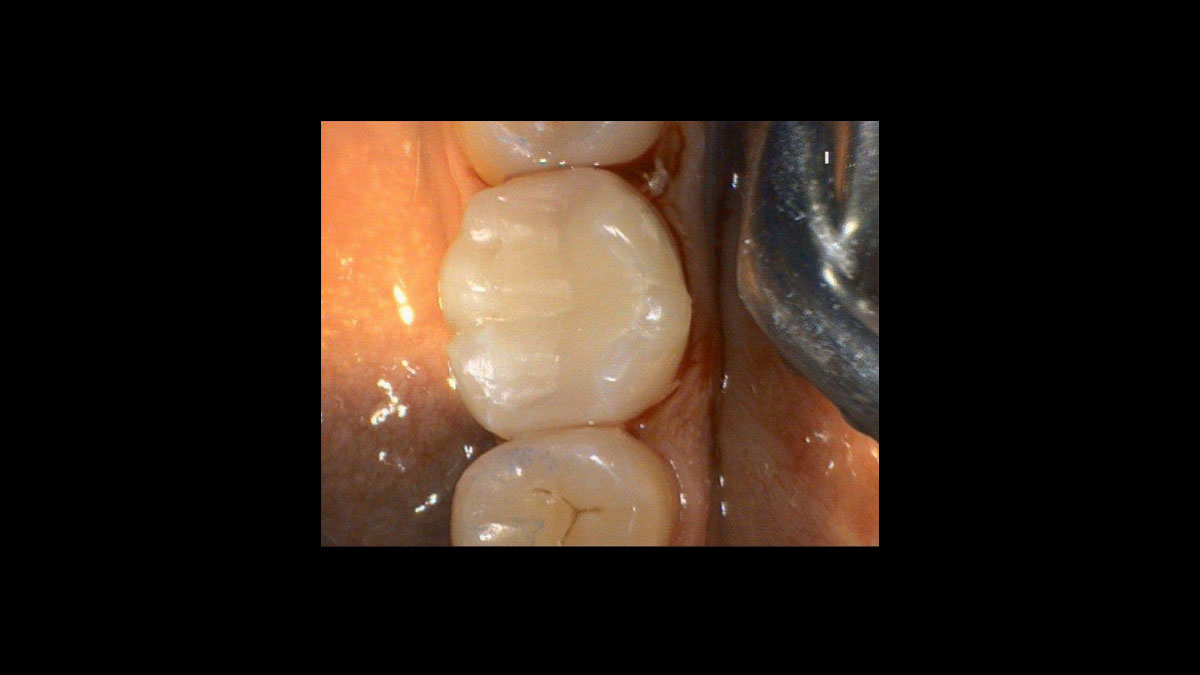

Periodoncia

Las siguientes aplicaciones se presentan en los videos y las imágenes:

• Reducción de gérmenes en periodoncia

Reducción de gérmenes en periodoncia